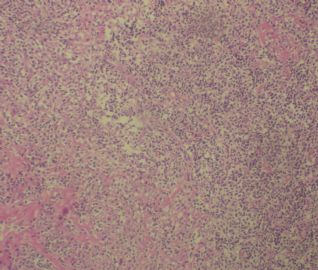

标本名称:  左前臂数个大小不等的皮下肿物。

既往有非何杰金淋巴瘤(滤泡性淋巴瘤)病史22个月。

• 左前臂数个大小不等的皮下肿物     淋巴瘤?图2

图2

病例不错。细胞胞浆透亮,间质血管丰富,图片不是很清晰,似乎有嗜酸粒细胞?

恶性,首先考虑T-NHL。IHC证实。

既往有NHL病史,图片不太清晰,细胞弥漫,胞浆透亮,首先考虑T细胞淋巴瘤。